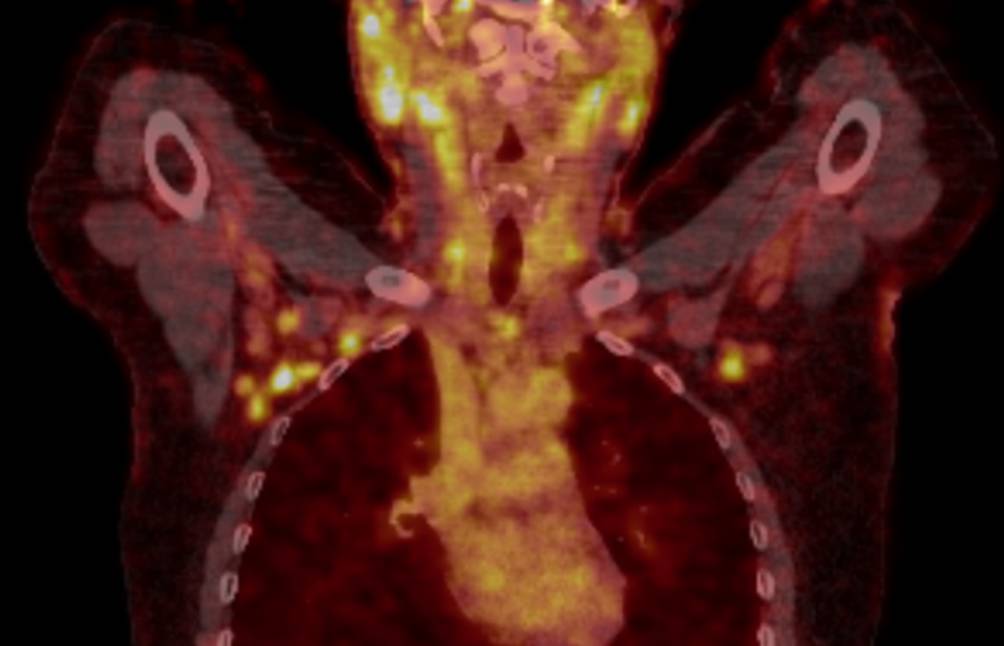

Die Durchführung des 18F‑FDG-PET/CT, welches im Rahmen der mittlerweile bekannten Sarkoidose veranlasst wurde, ergab ein sehr vergleichbares Bild mit multiplen Lymphnoten mit pathologisch erhöhtem Glukosemetabolismus, welche durchaus mit einer aktiven granulomatösen Erkrankung in Einklang zu bringen waren (Abb. 3).

Abb. 3

18F‑FDG-PET/CT: Hypermetabole Lymphknoten bihilär, vereinbar mit einer aktiven granulomatös-entzündlichen Erkrankung